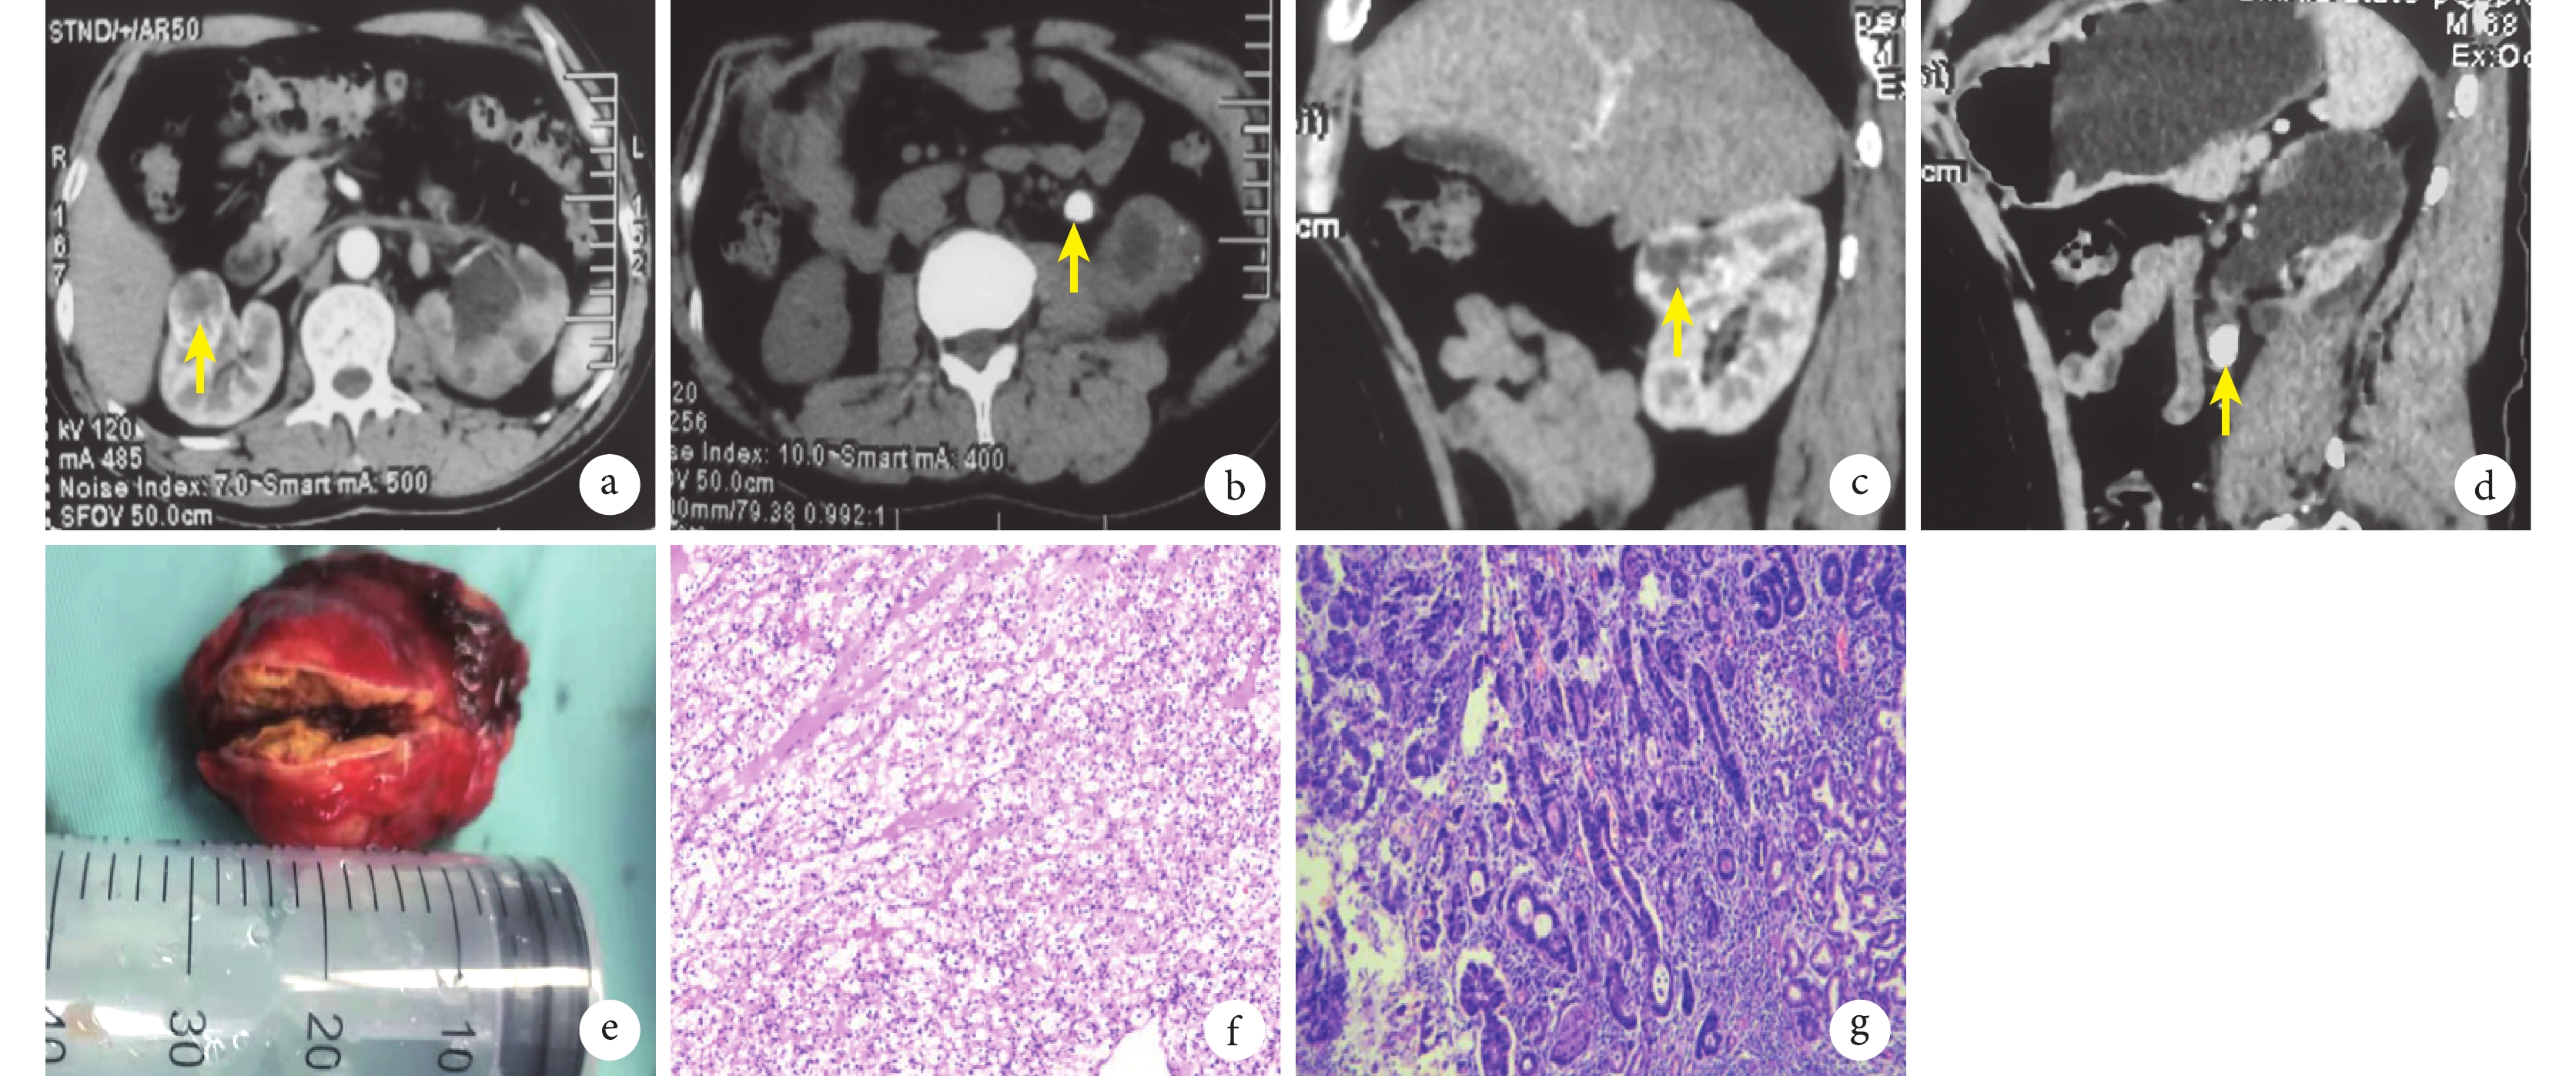

a: CT橫斷面見右腎腫瘤(黃箭);b: CT橫斷面見左腎輸尿管結石(黃箭);c:CT矢狀面見右腎腫瘤(黃箭);d:CT矢狀面見左腎輸尿管結石(黃箭);e:示右腎腫瘤手術標本;f:腎腫瘤術后病理學檢查提示為RCC(HE染色 ×40); g:胃腫瘤術后病理學檢查提示為高-中分化腺癌(HE染色 ×40)

患者,男,69歲,因“體檢發現右側腎占位,左側輸尿管結石8 d”入院。病史無特殊,查體未見明顯異常。入院前腹部及盆部CT檢查提示: ① 右腎占位性病變,考慮腎癌可能;② 左側輸尿管上段結石并腎及輸尿管積水;③ 左腎萎縮、左腎多發小結石。B超檢查提示:右腎中部見約4.4 cm×3.2 cm大混合回聲,形態規則,邊界清楚;左側輸尿管上端內徑約1.1 cm,內探及多個強回聲,后方伴聲影,較大者直徑約1.4 cm。胃鏡檢查提示:胃底體后壁區域黏膜粗糙、糜爛,苔不均勻覆蓋,質軟,觸之易出血。活檢組織病理學檢查提示:(胃底-體后壁組織)黏膜慢性炎癥,腺體高級別上皮內瘤變,部分區域癌變為腺癌。實驗室檢查:肌酐 124.4 μmol/L,腫瘤標志物均為陰性,余未見明顯特殊。初步診斷為右側腎腫瘤,左側腎積水伴輸尿管結石(圖1a~1d)和胃惡性腫瘤。

經多學科討論,綜合考慮患者及家屬意愿后,建議先處理右側腎腫瘤和左側腎輸尿管結石,待患者體能恢復后再行胃癌手術。遂患者于全身麻醉下先行腹腔鏡左輸尿管切開取石+右腎部分切除術。術中探及結石位于左腎與輸尿管交界處,經腹膜后行腹腔鏡下輸尿管切開取石術。取石結束后變換體位,腹腔鏡下經腹膜后游離顯露出右腎腫瘤,見腫瘤約3.5 cm×3 cm×3 cm大(圖1e),位于右腎前唇,行腹腔鏡下腎部分切除術。術后病理報告:①(右腎)腎透明細胞癌(renal cell carcinoma,RCC),3.5 cm×3.5 cm×3 cm大,WHO/ISUP核級分類為2級,切緣未見癌侵及;② 右腎門淋巴結(0/2)未見癌轉移(圖1f)。

患者術后恢復良好,于術后40 d再次行腹腔鏡輔助下近端胃切除術+D2淋巴結清掃、食管-胃吻合術。術中探查腹腔內無異常結節。根據術前檢查結果確認腫瘤位于胃體近賁門處,病灶范圍為2.5 cm×3 cm,未侵犯漿膜層,胃小彎側和胃大彎側未見淋巴結腫大。術后病理報告:(近端胃)高-中分化腺癌,Lauren分型為腸型,腫瘤侵犯黏膜肌層,病灶累積范圍4 cm×3.5 cm,脈管、神經未見明確受累;上、下切緣未見癌侵及。經免疫組化 (CKB/18)染色證實,淋巴結(0/18) 未見癌轉移,分別為小彎網膜淋巴結(0/18) ,大彎網膜淋巴結(0/0),見圖1g。